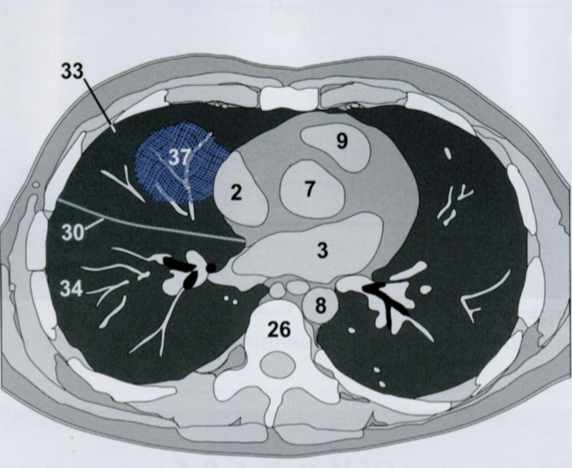

На снимке в правом легочном поле мы видем участок инфильтрации. Справа легкое имеет три доли. В данную проекцию попадают СД и НД. В какой из них расположена инфильтрация и почему Вы пришли к такому выводу?

Запомните: если на фоне измененного легочного рисунка виден силуэт сердечной тени - затенение распологается в заднем отделе НД, а если силуэт не определяется - в переднем отделе СД.

КТ на уровне правого предсердия (2), с инфильтрацией (37) в СД (33), которая соприкасается с ПП (2).

Инфильтрация и окружающих отек повышают плотность легочной ткани до плотности, эквивалентной сердечной тени.

В результате граница между инфильтратом и контуром сердца не визуализируется.

Ответ: инфильтрат раполается в переднем отделе СД правого легкого.

26 - грудные позвонки

2 - правое предсердие

7 - восходящая аорта

9 - легочный ствол

3 - левое предсердие

8 - нисходящая аорта

30 - косая щель

33 - средняя доля

34 - нижняя доля